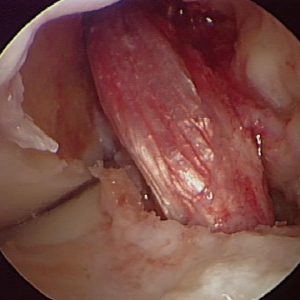

IMG_0933